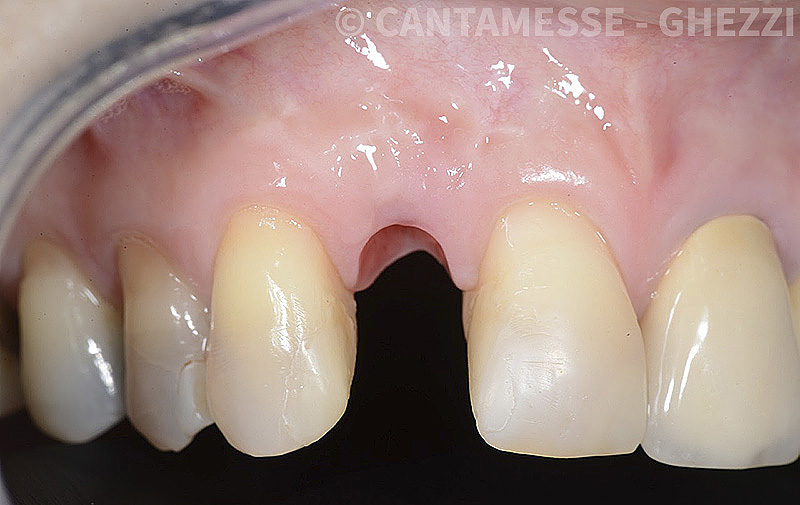

PREMESSA: in seguito all’estrazione dell’incisivo laterale superiore di destra, resasi necessaria per cause batteriche, si decide di affrontare il caso con il posizionamento di un impianto in sostituzione dell’elemento mancante dopo guarigione del sito infetto. Con tecniche rigenerative sia dei tessuti ossei mancanti a causa dell’infezione pregressa, sia dei tessuti gengivali che appaiono inizialmente troppo spostati in alto, si ripristina una corretta morfologia delle parabole (contorni) gengivali e delle papille interdentali (triangoli di gengiva tra due denti vicini).

Vengono utilizzati 2 tipi di provvisori: il primo, cementato ai denti vicini, viene utilizzato dal momento dell’estrazione del dente fino ad impianto osteointegrato (circa 6 mesi); il secondo, avvitato direttamente all’impianto, ha una funzione di prova estetica ma soprattutto di guida per la maturazione dei tessuti gengivali peri-implantari portandoli verso la maturazione completa prima di posizionare la corona finale in disilicato di litio.